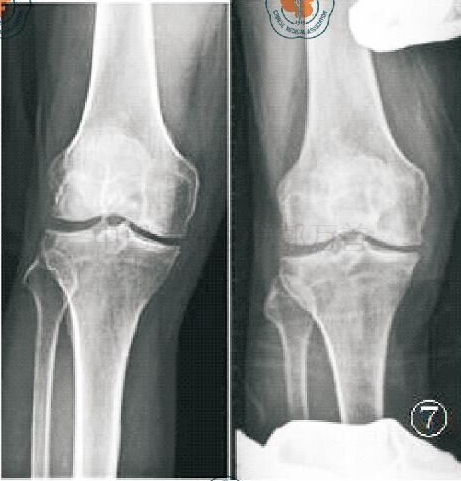

X线片一:术前前后位

标准的负重前后位 X 线可判断内侧间室关节软骨的磨损,若内侧间室关节间隙变窄,股骨内侧髁与内侧胫骨平台呈“骨对骨”接触状态,符合单髁手术适应证。